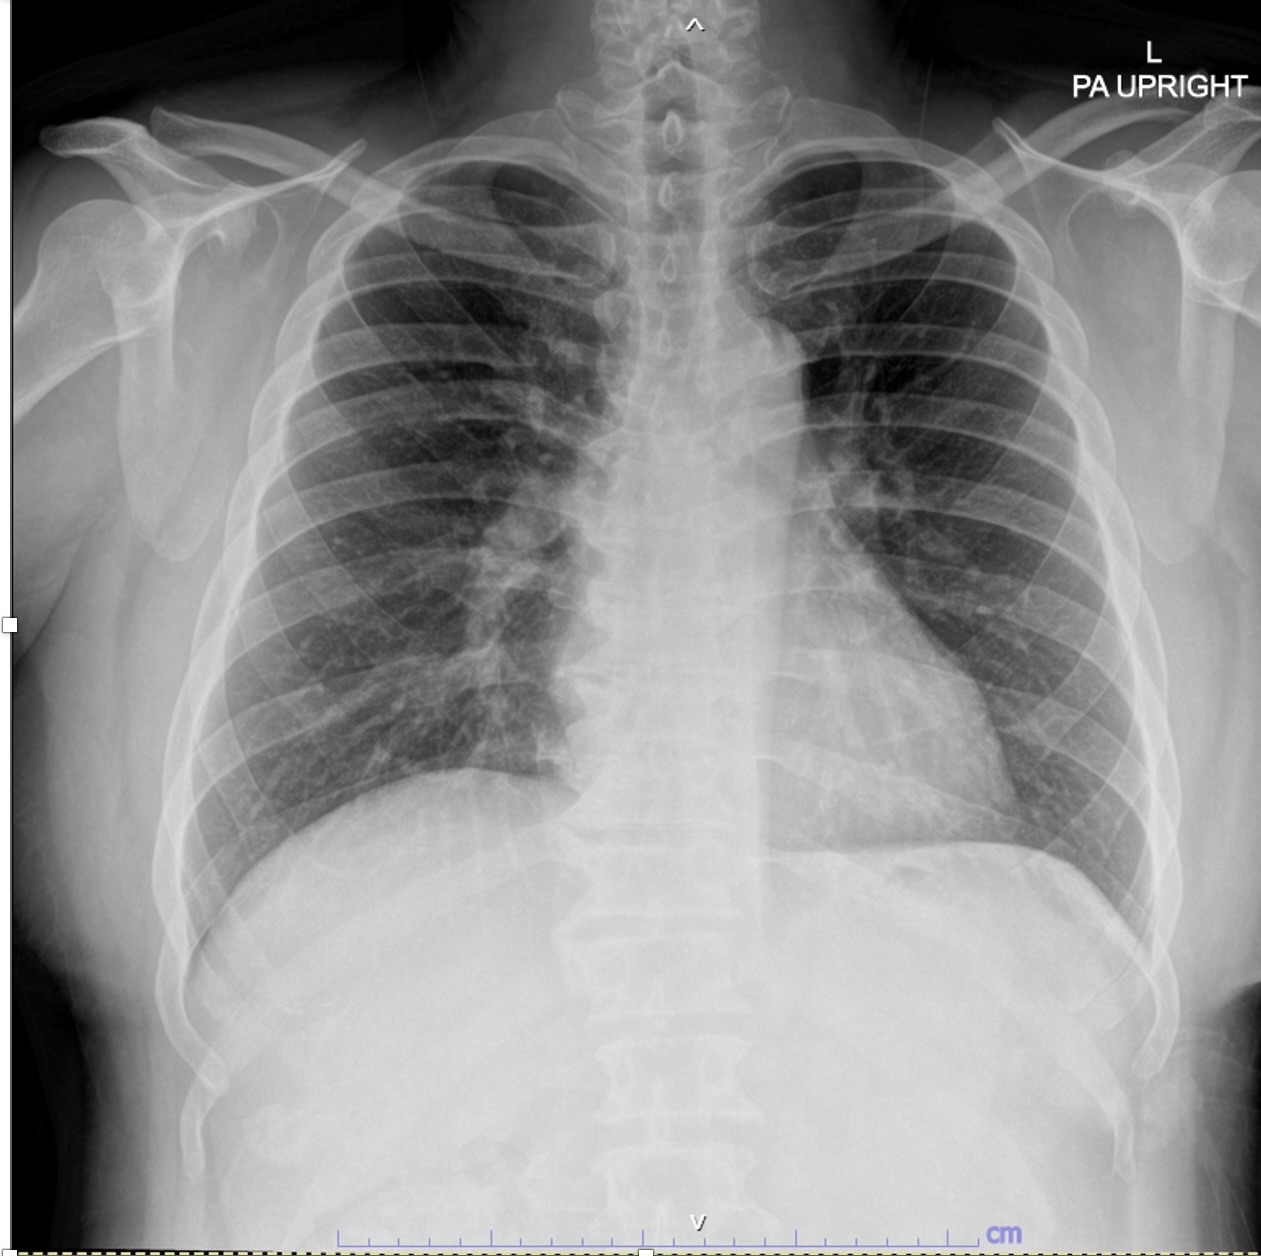

BUN 17.0, Cr 0.83, GFR 107 Electrolyte: Na 138, K 3.8, HCO3 21, CL 100 Anti-HCV, Anti-HIV, HBsAg: negative WBC 8050, Hb 13.5, Hct 40, PLT 245000 PT 12.4, PTT 23.5, INR 1.08 Echo: EF 60%, inferior and inferoseptal wall hypokinesia, no significant valvular abnormalities, no pericardial effusion